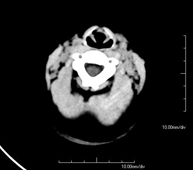

- Skull CT

Radiological test that provides high definition anatomical images of the skull (brain stem, cerebellum, cerebrum, cranial calotte, etc.) using CT (Computed Tomography) equipment. Indicated for: trauma, headache, memory disorders, sudden loss of strength in a limb or half of the body.